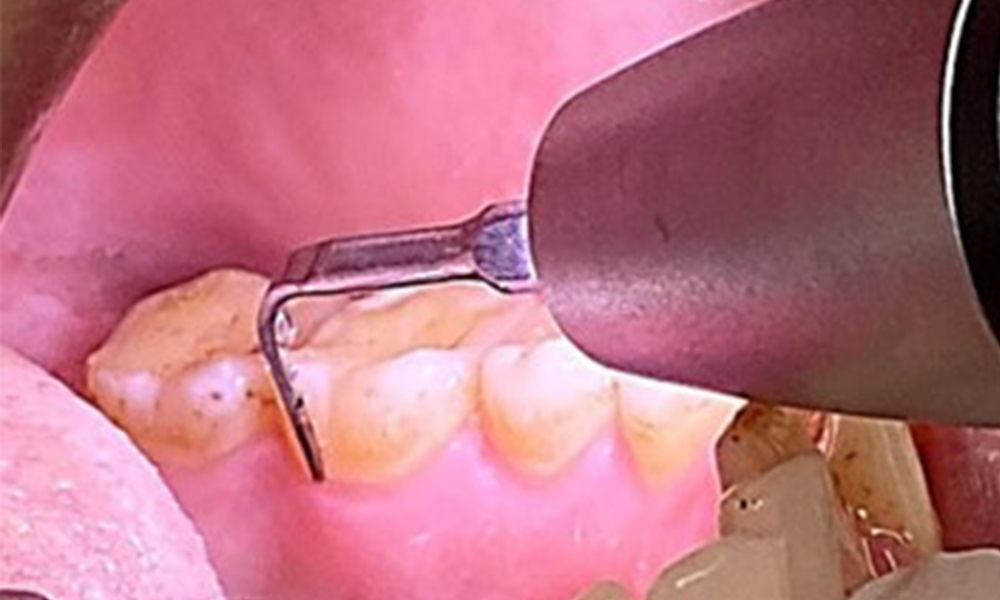

The objective would be to control disease risk by removing supragingival and subgingival biofilm. The instruments can be selected based on patient needs. First, calculus and any concretions must be removed using ultrasonic and/or manual instruments (Fig. 10).

Due to the otherwise favourable general medical condition, the needs determined during the intraoral examination will be decisive for their treatment. It will be essential to periodically determine the probing depths. Gingival bleeding decreases in smokers, which is why the clinical diagnosis of periodontitis can only be made by probing (Fig. 7). Placing exclusive focus on the determination of bleeding indices may obscure existing periodontitis or gingivitis. (5)